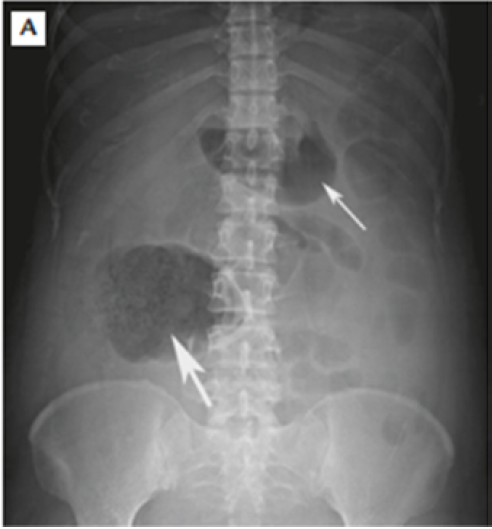

Large stomach distention shown in Figure 1

Figure 1: Large Stomach Distention